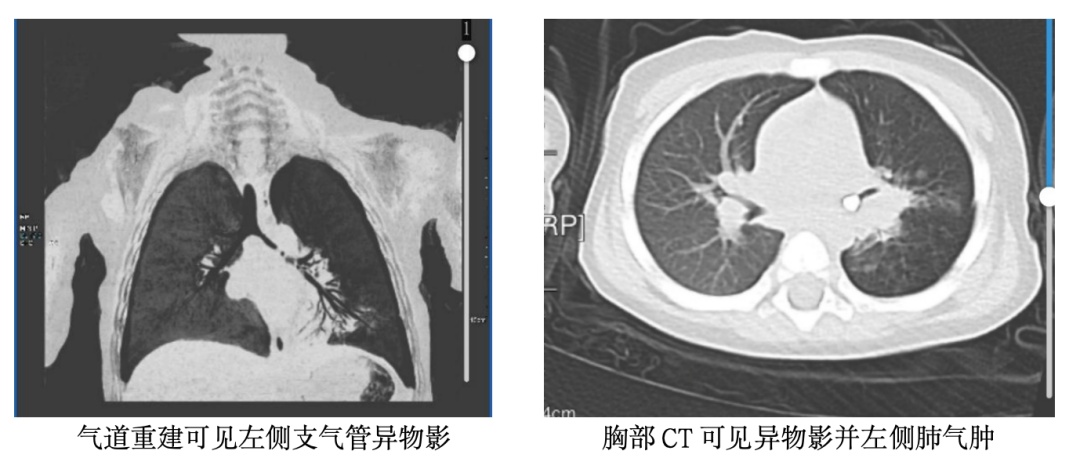

在外院完善CT检查后,真相终于浮出水面:孩子左侧支气管内,牢牢卡着那颗乳牙!异物长期堵塞气道,易引发严重的肺部感染、气道水肿,病情极其凶险。更让救治难上加难的是,因长期患病、营养摄入不足,宝宝还合并中度贫血,血红蛋白仅80g/L,身体耐受度极差,这也让后续的手术和麻醉风险成倍增加。

时间就是生命,家属紧急将孩子转至北京儿童医院接受专业救治。面对贫血、感染、气道梗阻三重高危因素,患儿的麻醉风险远高于普通儿童,稍有不慎就可能出现缺氧、循环波动、窒息等危险情况。万幸的是,在经验丰富的麻醉团队精准监护、精细操作下,为手术搭建起坚实的“生命安全防线”,最终医生在全麻下顺利完成气管异物取出术,将滞留气道50天的牙齿成功取出,孩子有惊无险渡过难关,目前正逐步恢复健康。